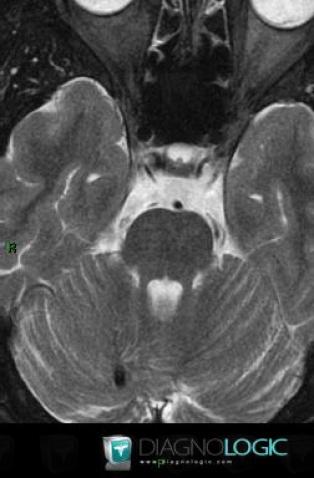

Voici les informations spécifiques à l'image clé ci dessus:

- Diagnostic Anomalie veineuse de développement, Localisation(s) Fosse postérieure, comportant les gammes Lésion infratentorielle en hyposignal T2 ou FLAIR